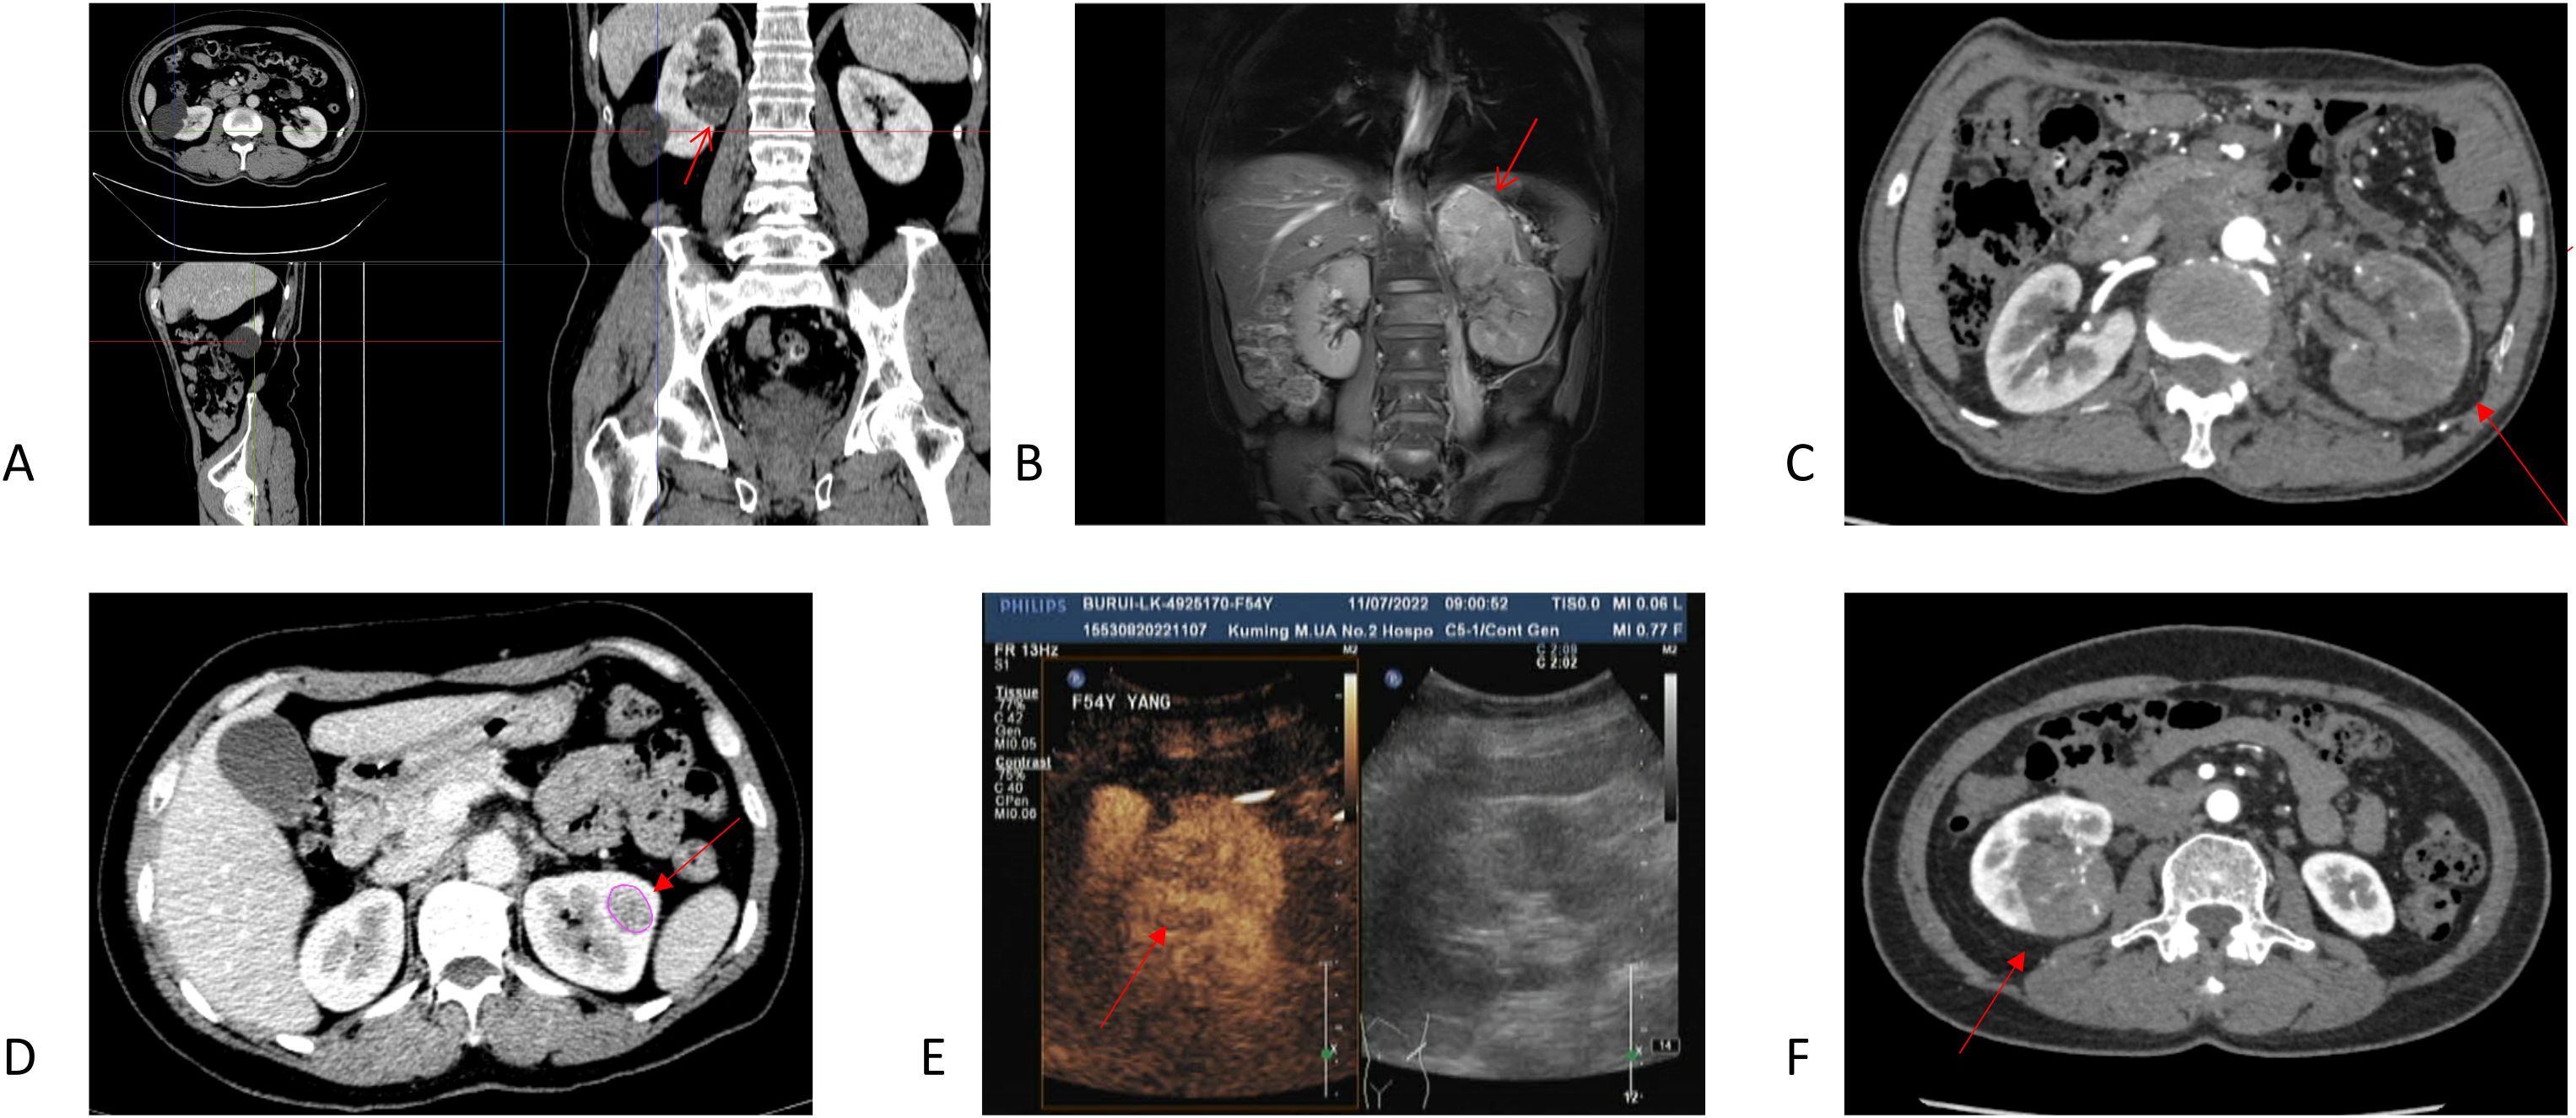

Figure 2

Figure 2. Imaging and gross findings of Case 5. (A) The solid components of the tumor showed mild post-contrast enhancement. (B) On MRI, the left renal lower pole showed a slightly hypointense signal on T1WI and a slightly hyperintense, heterogeneous signal on T2WI. A prominent T1-weighted contrast-enhanced signal was observed, suggesting possible intratumoral hemorrhage. (C) Gross pathology: The kidney was completely dissected with easily separated capsule and fat. The cut surface revealed gray-red to gray-brown masses in the renal pole, with indistinct borders from the surrounding parenchyma. The tumor appeared to invade the renal sinus but not the renal pelvis. (D, E) Recurrence on PET-CT: PECT-CT examination showed recurrence: a small amount of fluid accumulation in the left nephrotomy area and multiple occupancy, with increased FDG uptake; the size of the adjacent peritoneum was approximately 2.6 × 1.7 cm, the SUVmax was approximately 10.1, and the size of the renal area after surgery was 4.5 × 3.7 cm, and the SUVmax was approximately 12.

A 29-year-old pregnant woman was initially identified with a large left renal cyst (12.4 × 8.6 cm) during a pre-pregnancy examination 40 days prior. She presented with a complaint of occasional lumbar pain exacerbated by exertion. Enhanced CT revealed a 12-cm non-enhancing cystic lesion in the upper pole of the left kidney and a separate 8-cm solid, heterogeneously enhancing mass in the middle-lower pole. The presence of retroperitoneal lymph node metastases was also noted. The patient underwent a left radical nephrectomy. Final histopathological diagnosis was ESC-RCC, with a pathological stage of pT3aN1Mx. Because of limited hospital resources, genetic testing was not performed. The 5-month postoperative examination showed no signs of recurrence. However, at the 10-month follow-up, tumor recurrence was detected, which was subsequently confirmed by PET-CT (Figure 2).

The primary treatments for ESC-RCC are radical nephrectomy (3/5) and partial nephrectomy (2/5). Among five patients followed postoperatively, three achieved tumor-free survival (including one receiving chemotherapy), one died, and one experienced recurrence. In Case 4, the attending physician used sunitinib as systemic chemotherapy, and a similar chemotherapy regimen has been reported. However, the effect varied according to the extent of systemic metastasis of the primary tumor (26). Cases reported by Sakhadeo et al. highlighted manifestations of tumor metastasis (27). In the case study presented here, Case 3 was diagnosed with perirenal, retroperitoneal lymph node, and adrenal metastases at admission, along with venous tumor thrombus formation, indicating a very poor prognosis. Case 5 showed suspected minor lymph node metastases preoperatively but relapsed 10 months postoperatively (Figure 2). The patient is currently undergoing outpatient follow-up and plans to visit the oncology department for chemotherapy evaluation. These clinical outcomes underscore the need for more clinical data to better understand its biological behavior.